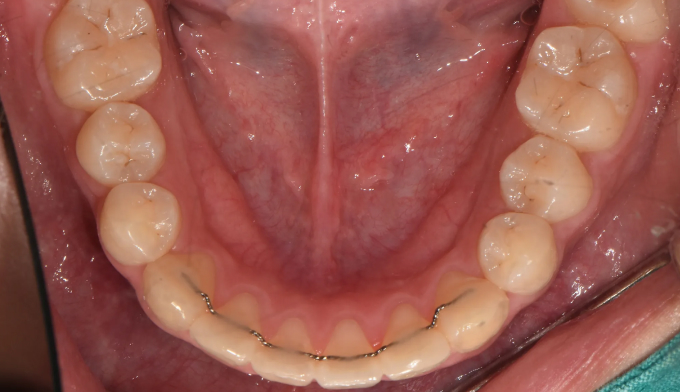

After